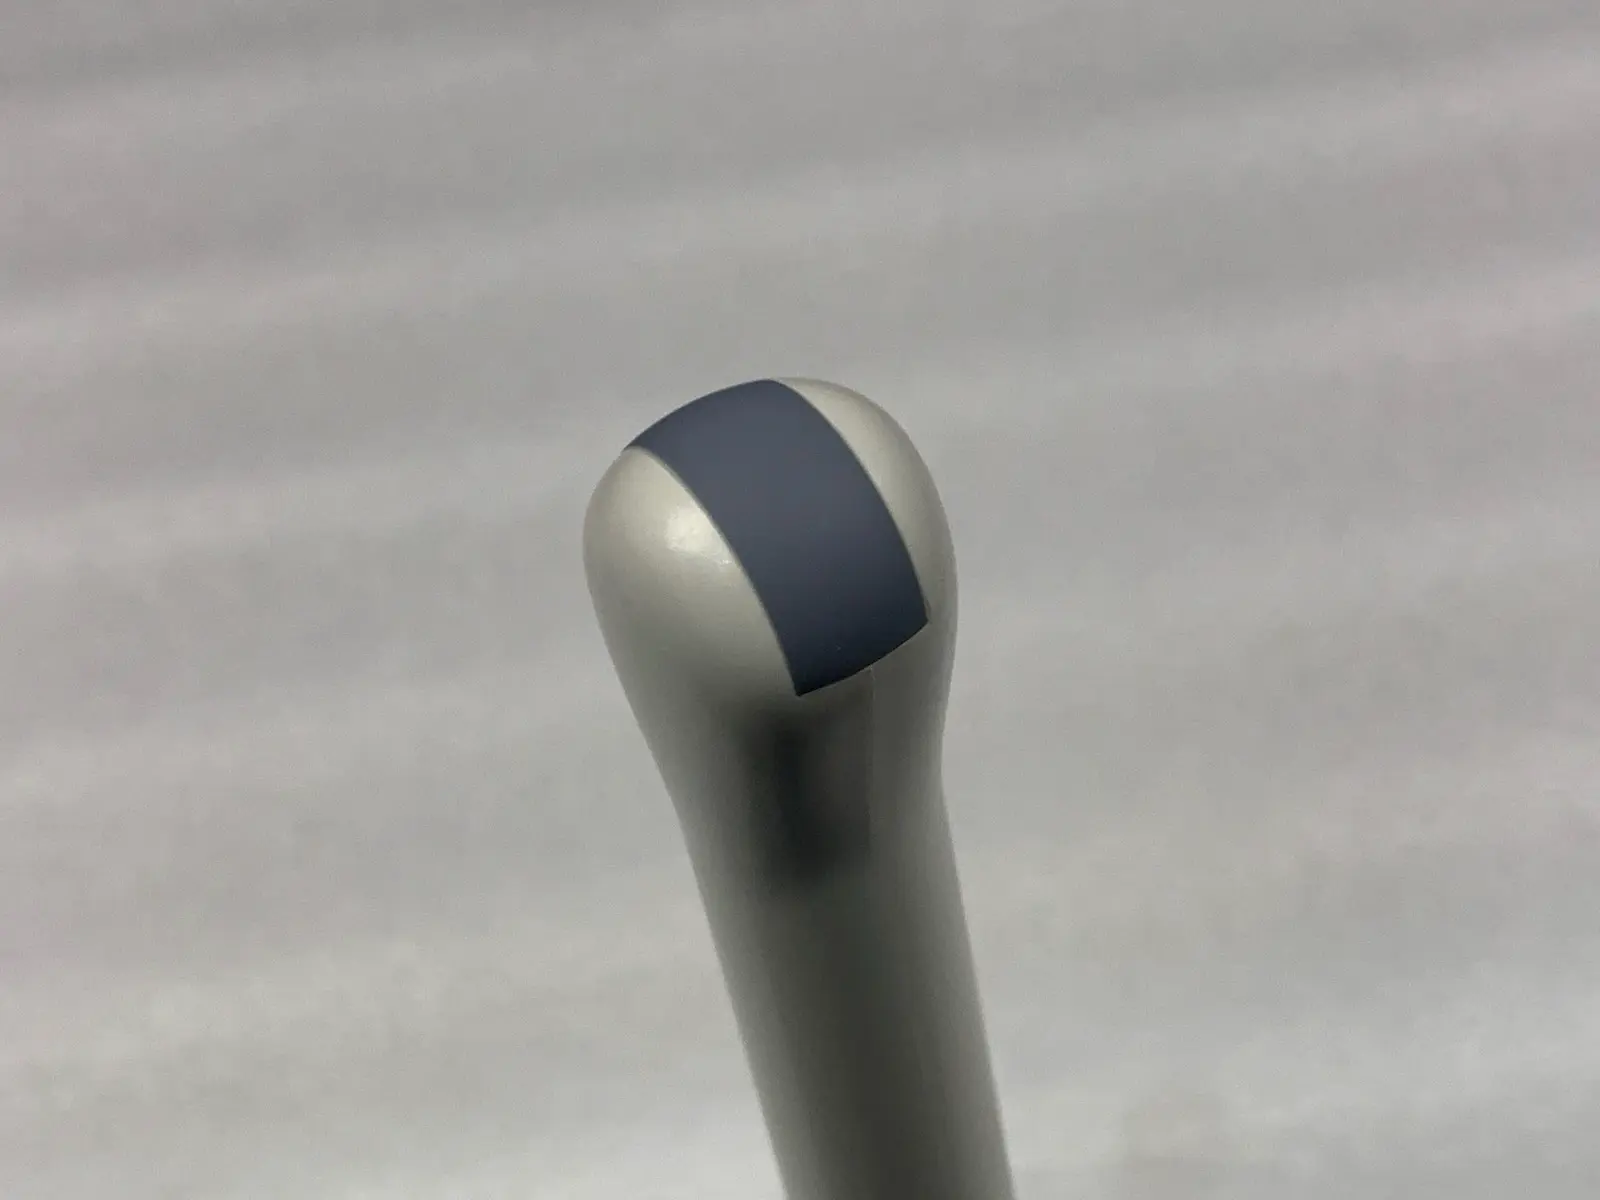

Acoustic Window (Lens): Appears clean and intact with no significant delamination or pitting visible in photos.

Blemish : Some cosmetic blemishes

Photos of this listing are of the actual item for sale.